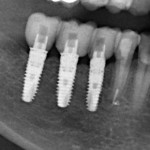

Я немного расскажу о пользе немедленной имплантации: